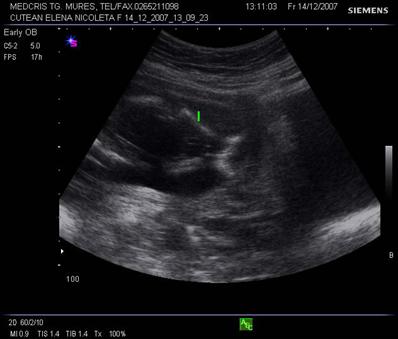

Aspecte normale ecografice in trimestrul II si III de sarcina